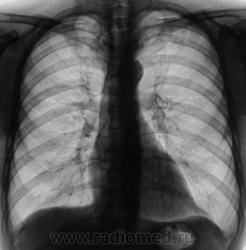

Динамика через 2 месяца после специфического лечения.

Пациент прислан был на контроль. Первично, был выявлен после прохождения профилактической флюорографии.

Ниже снимки до лечения.

Валентин Львович! Динамика, конечно, слабая. Но "Его Величество" не всегда адекватно реагирует на проводимую терапию. Или это изменения после перенесенного "Его Величества".  Склоняюсь к мысли слабо положительной динамики после проводимой специфической терапии.

Спасибо за высказанное мнение. Мы тоже отметили некоторую положительную динамику.

Пневмосклероз без динамики. Очаговых изменений не видно. Неужели подтвержден туберкулез?

При первичном обследовании туберкулёз подтвержден. Подтвержден и посевом на средах.